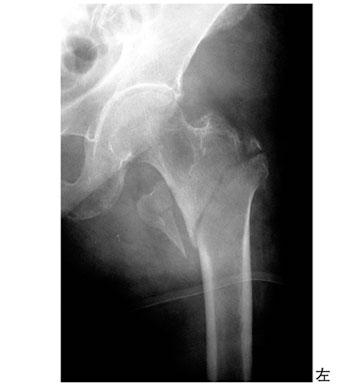

78歳の女性。自宅玄関で転倒してから起立歩行不能となり救急搬送された。来院時の単純エックス線画像を示す。最も考えられるのはどれか。

1

股関節脱臼

2

大腿骨頸部骨折

3

大腿骨骨頭骨折

4

大腿骨転子下骨折

5

大腿骨転子部骨折